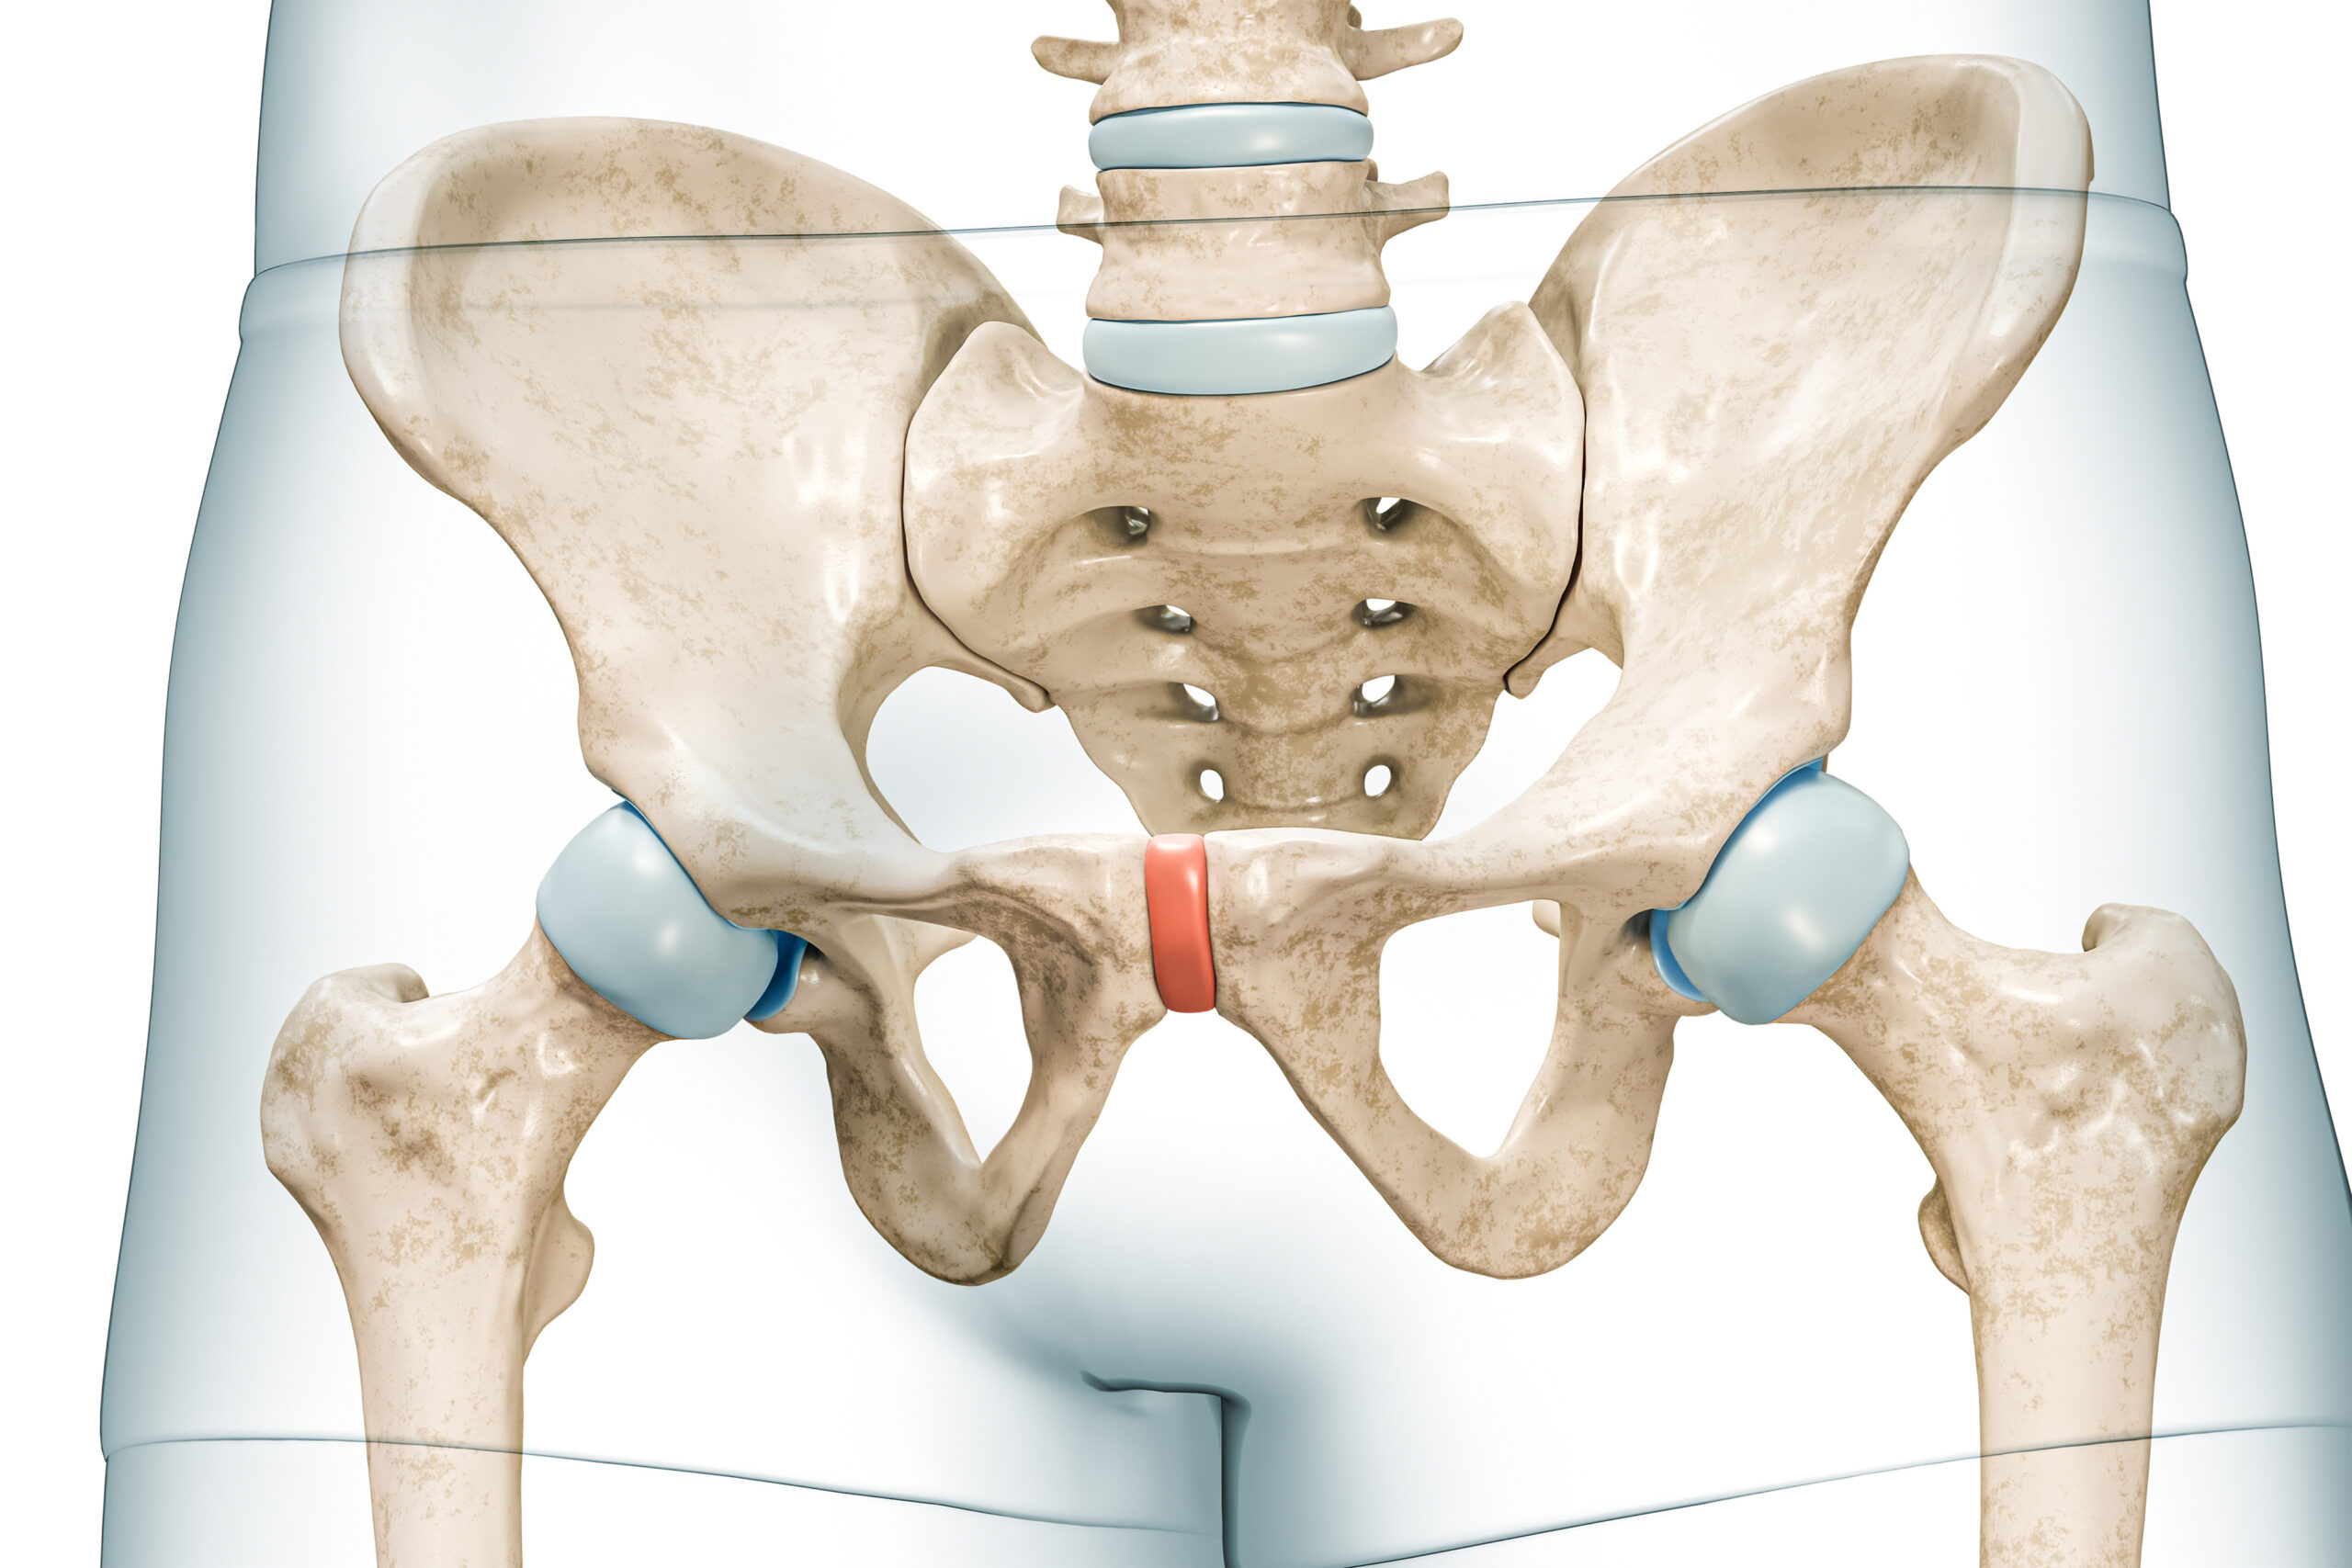

Dennoch ist der Schmerz real. Er kann ziehend, stechend oder dumpf sein und strahlt oft in den unteren Rücken, die Leisten oder die Oberschenkel aus. Da das Becken ein komplexes Geflecht aus Nerven, Muskeln, Bindegewebe und Organen ist, können die Auslöser vielfältig sein. Chronische urogenitale Schmerzen stellen ein eigenes Krankheitsbild dar, bei dem das Schmerzgedächtnis des Körpers oft eine zentrale Rolle spielt.

Nach dem Gespräch folgt eine behutsame und gründliche körperliche Untersuchung. Unser Ziel ist hierbei die sogenannte Ausschlussdiagnostik. Wir untersuchen die Beckenorgane, die Beckenbodenmuskulatur und die angrenzenden Strukturen, um sicherzustellen, dass keine akuten Entzündungen, Endometriose-Herde oder strukturellen Veränderungen vorliegen, die einer anderen spezifischen Behandlung bedürfen.

Wir untersuchen dabei nicht nur „organzentriert“, sondern achten auch auf muskuläre Verspannungen und myofasziale Triggerpunkte im Beckenbereich, die oft maßgeblich an der Schmerzentstehung beteiligt sind.